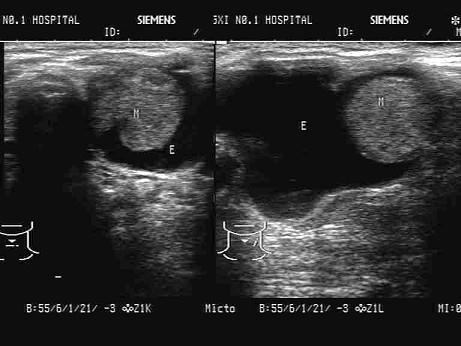

问题 患者,女,65岁,近半月颈部明显增大。超声检查如图,最可能的诊断为?(?)

选项 A.甲状腺囊肿 B.结节性甲状腺肿 C.甲状腺腺瘤并囊变 D.甲状腺乳头状囊腺癌 E.甲状腺炎

答案 D